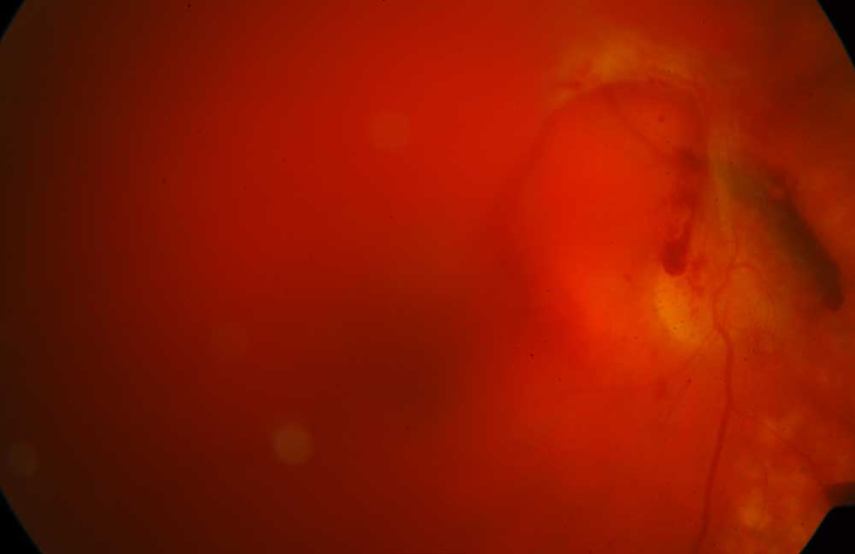

증식성 당뇨망막병증

당뇨망막병증이 계속 진행하여 신생혈관이 발생하게 되면 증식성 당뇨망막병증이라고 합니다. 신생혈관이 파열되어 심한 유리체출혈, 망막앞출혈이 발생하여 갑작스런 시력저하가 발생할 수 있으며 신생혈관의 섬유조직이 자라서 유리체수축을 일으키고 이로 인해 견인성 망막박리가 발생합니다. 간혹 신생혈관 녹내장이 발생하여 심한 통증을 유발하기도 합니다.